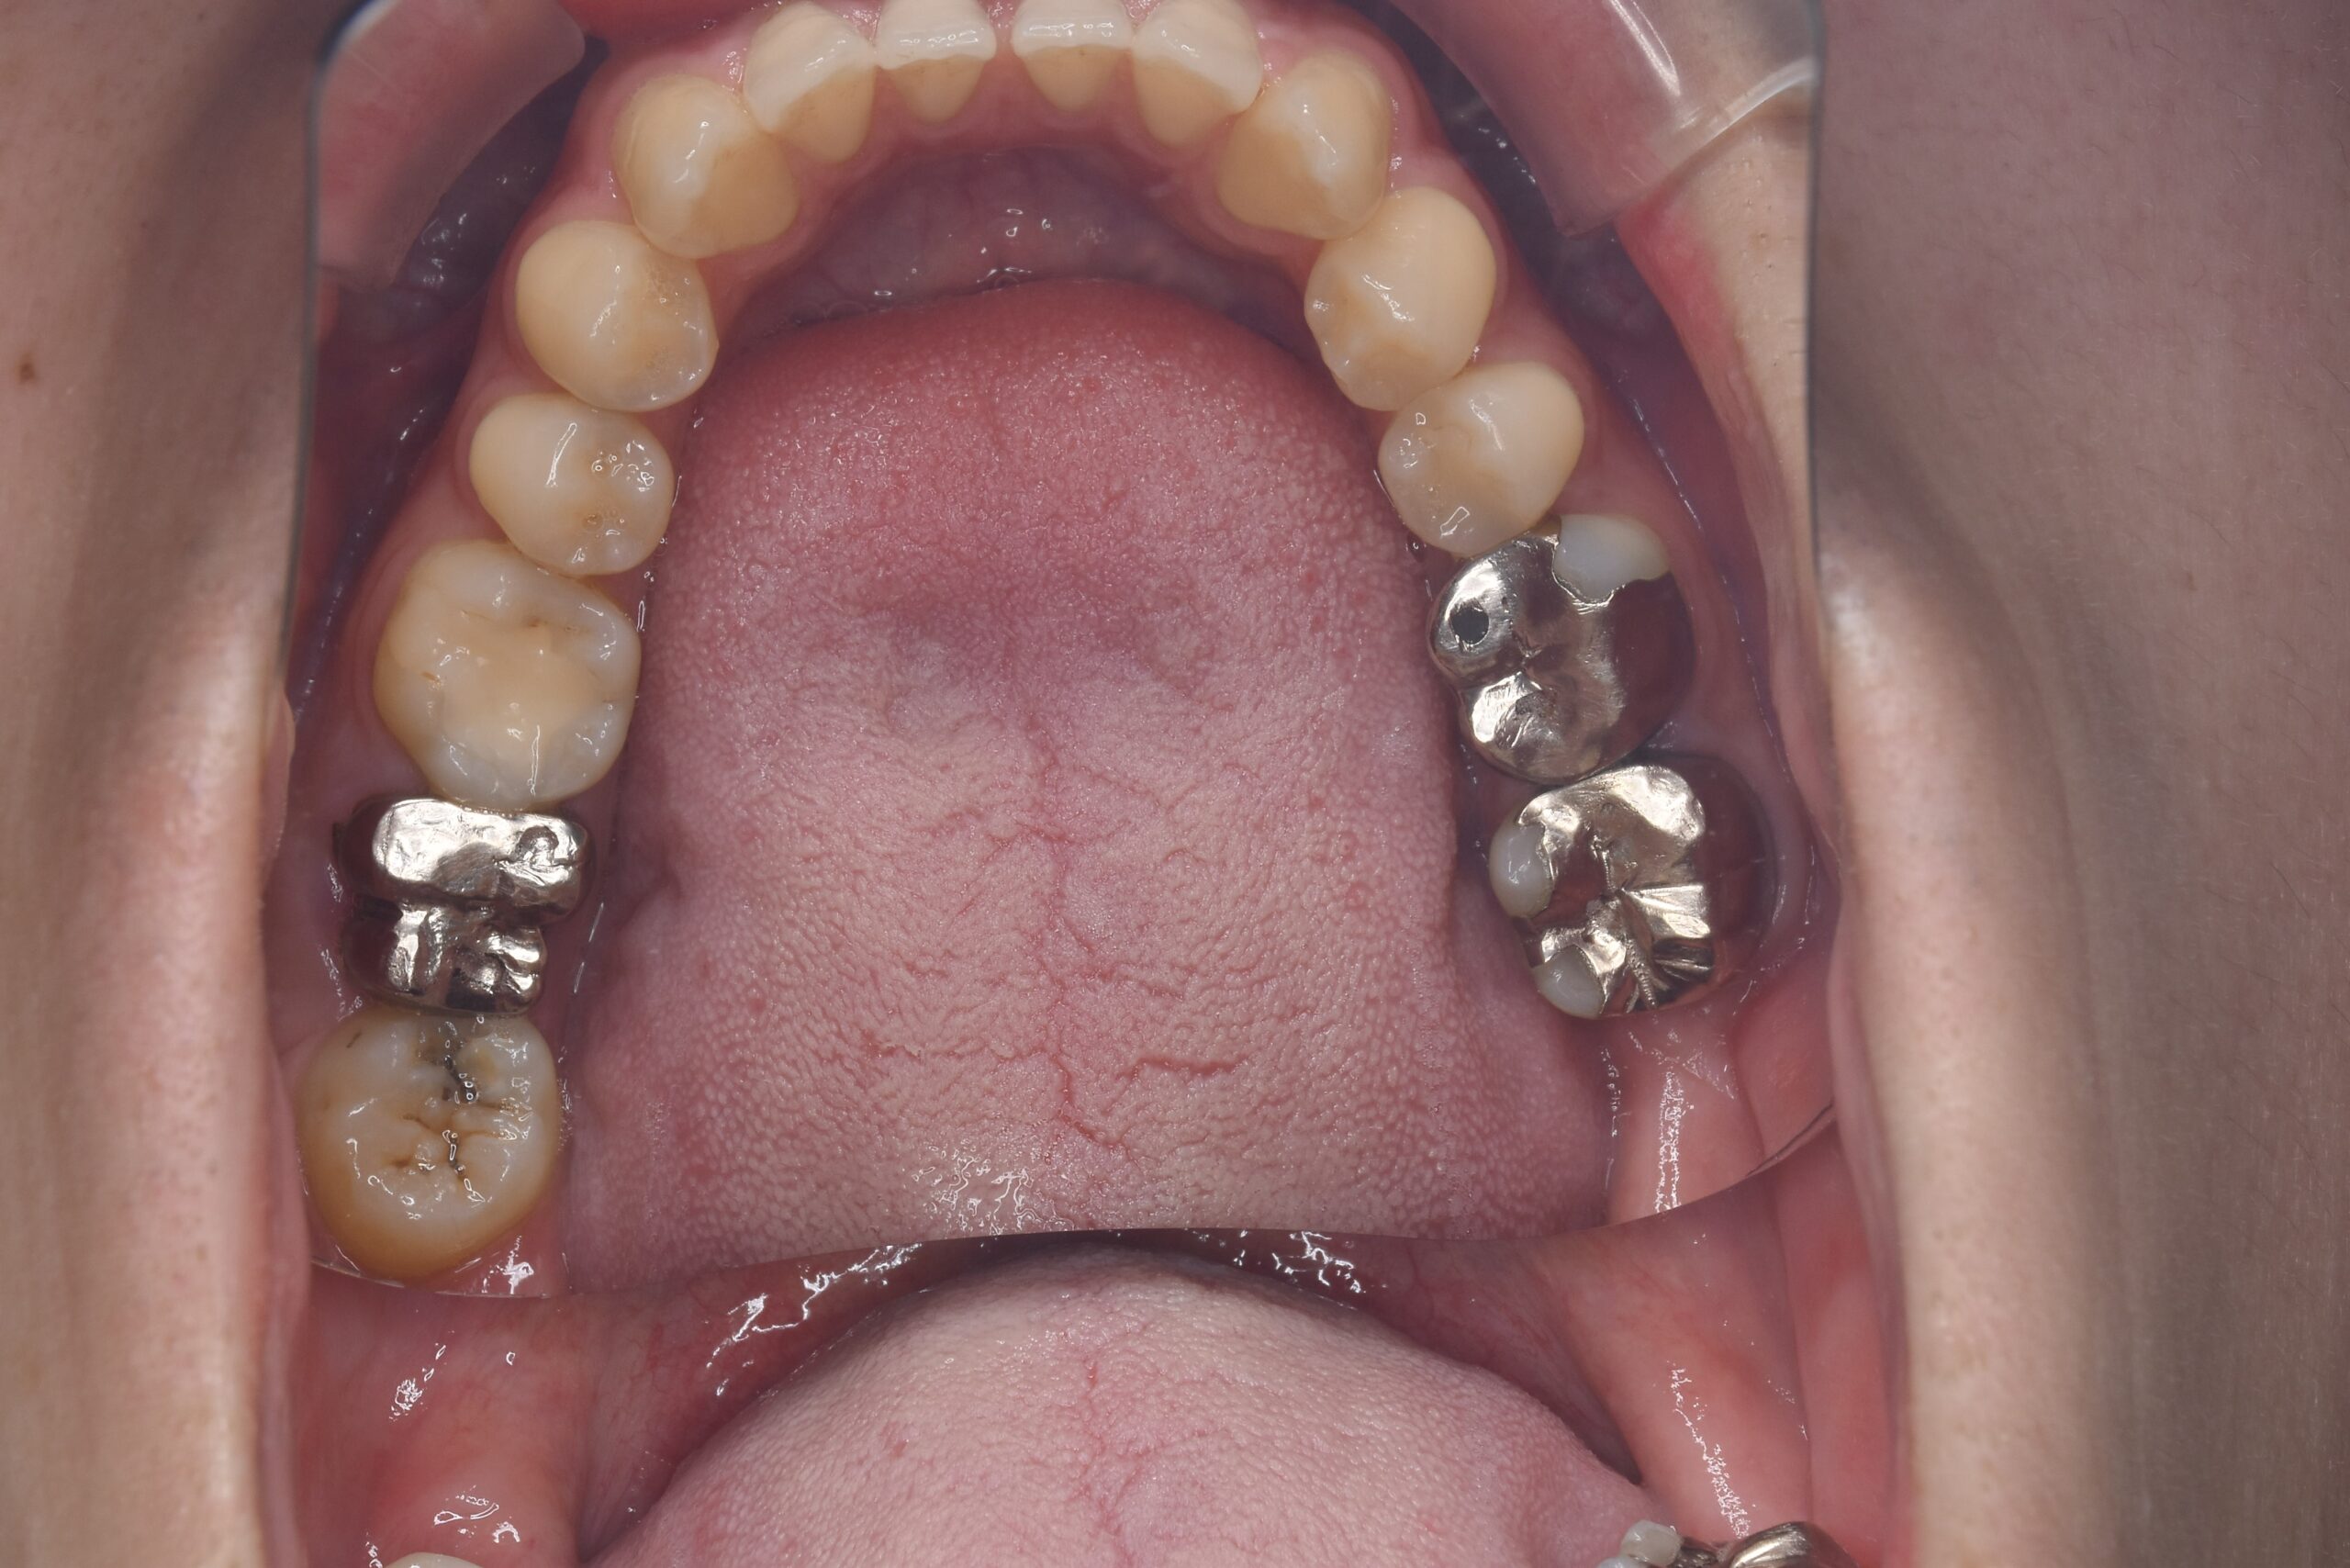

After